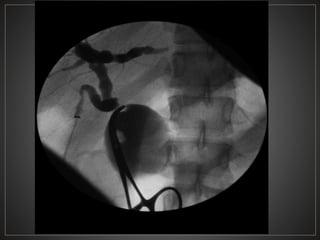

ENF. DE CAROLI:Dilatación sacular CONGENITA y segmentaria de los CBIH SX. DE CAROLI: Dilatación del conducto cístico+ Fibrosis hepática.

CPRE: Dilataciones saculares de CBIH. TC: Simple:Áreas redondas, hipointensas en topografía de CBIH. Contraste: Signo del punteado central. RM: T2: Espacios quísticos hiperdensos

• #51 La colangiografía transhepática percutánea muestra una dilatación sacular generalizada de los conductos biliares intrahepáticos y extrahepáticos.